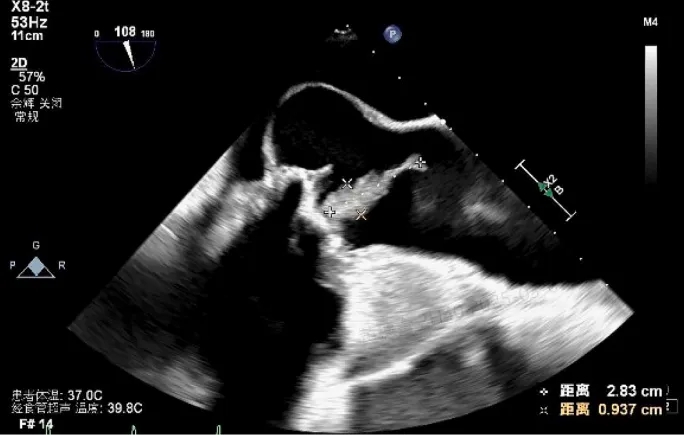

经胸超声心动图提示:人工主动脉瓣可见赘生物(29×9mm,活动度大,且随心动周期显著摆动)(图1);重度瓣周漏;瓣叶撕裂并伴有广泛瓣周脓肿形成。主动脉根部扩张,无冠窦明显膨出,并可见右冠窦至右心房瘘管形成。其余可见严重二尖瓣反流、中度三尖瓣反流及三尖瓣上赘生物附着。

图1